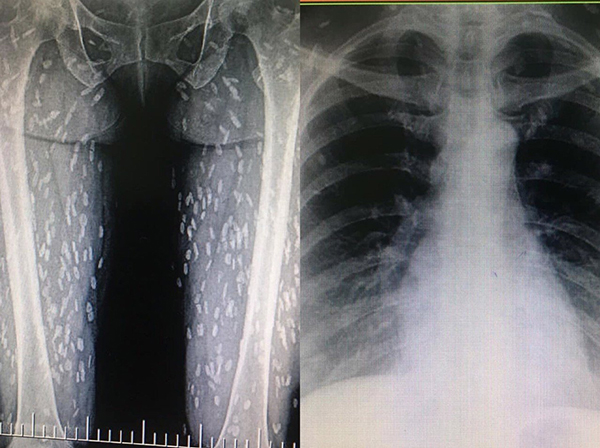

(曼谷2日综合电)泰国一名女子时常生吃猪肉,后来感觉身体不适前往医院检查,一照X光才发现,体内竟然有数百条寄生虫,宛如一片“白斑”。

泰国一名女患者,也因为生吃猪肉而染病,女患者在医院照X光,其结果显示双腿内有上百条寄生虫,像是白斑一样满布双腿,照片曝光后让不少人都怵目惊心。

猪肉绦虫卵可在小肠孵化接着移到身体或内脏等组织;最常见的囊虫位置在皮下组织及肌肉,如果感染到脑部、眼睛或脊髓,会引发严重后遗症,甚至可能导致癫痫发作,需立刻就医。先前泰国也有其他案例,一名男子喜欢吃半熟的肉类,结果就医后从体内拉出4公尺长的绦虫,也曾引发热议。